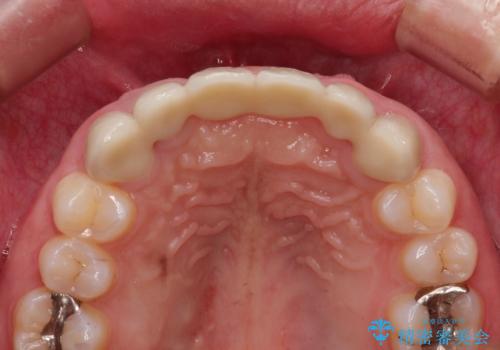

- 数ヶ月前に治療終了したブリッジの歯ぐきの違和感が強く、改善を求めて来院されました。

歯ぐきは著しく腫れ、少し触ると出血してしまうような状態であったためブリッジの再作製・歯周外科を用いた歯肉環境の改善を計画します。